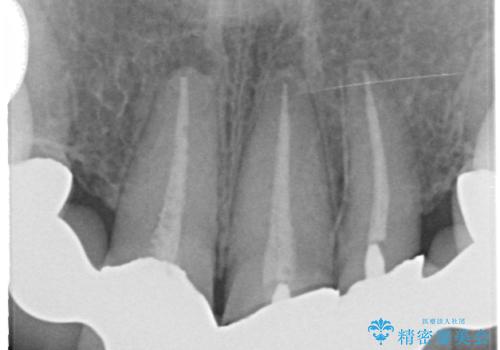

左上4番目の歯から右上3番目の歯まで計7歯のクラウンを除去し、オールセラミッククラウンによる補綴を行いました。

根管治療の注意事項(リスク・副作用など)

- 根管治療により類似の全ての症例の問題が解決するわけではなく、症例はあくまでも一例です

- 根管治療により痛みや腫れがひかない事や、術後に痛みや腫れが生じる事、治療によるファイル破折やパーフォレーションなどの偶発症、術後の歯根破折を生じる可能性もあります